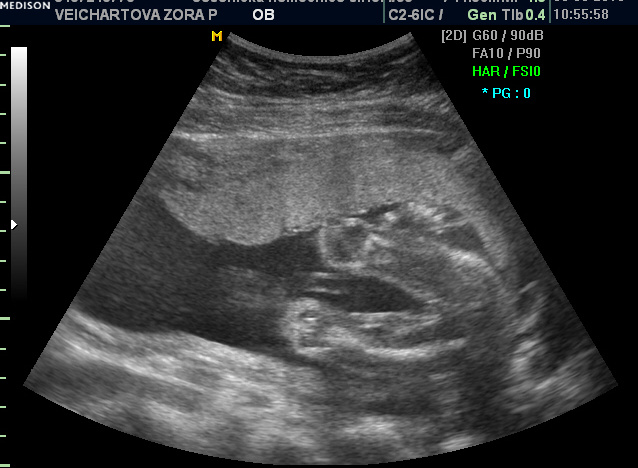

posílám dvě fotečky a snad to - zkušené maminky - poznáte ;-)

Zorko, jelikož tam nevidím vůbec nic, tedy myslím žádné varlátka, tak to vypadá na holku

. Nebo nejsem zkušená maminka

Holkaaaaa ...

To je super, ze vam to vyslo!! Tedy snad se nepletu, ale tam ten pindik proste neni;-) A jsem rada, ze je vse v poradku.... tedy ja snad budu mit dva kluky sama

Teri, on se zas nějaký klučík narodí :-) taky jsem čučela jak puk! Posledně na tom samém místě- to není holčička, a dneska naopak :-) Teri, já si fakt myslela, že je tam kluk a pořád tomu nevěřím na 100%, ten první kluk byl přece jen jasný :-))) ale doktorka je zkušená a říkala mi 99,9% holka. No téééda :-) Erik dnes přes den nespal a tak aspoň večer vytuhl chvilenku po osmé :-)